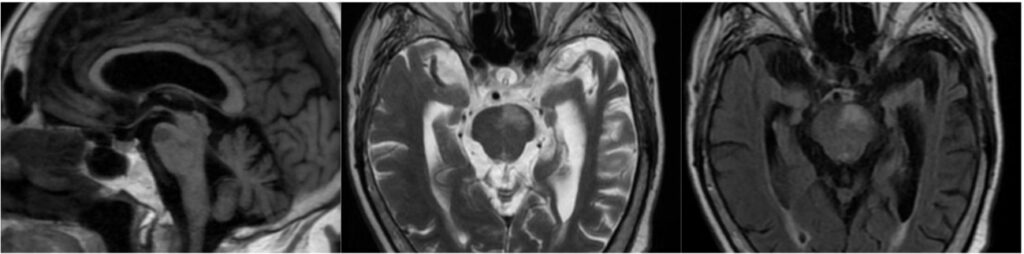

La lesión se localiza en la porción dorsolateral del bulbo raquídeo, generalmente en el territorio irrigado por la arteria cerebelosa posteroinferior, identificable en resonancia magnética como un foco hiperintenso en secuencias T2 y FLAIR, con restricción a la difusión y disminución de la señal en el mapa ADC en la fase aguda. La afectación del pedúnculo cerebeloso inferior y de los núcleos vestibulares, habitualmente en el bulbo lateral rostral, explica el vértigo y la ataxia ipsilateral, mientras que el compromiso del núcleo y tracto espinal del nervio trigémino, de disposición posterolateral, se traduce en pérdida de la sensibilidad termoalgésica facial ipsilateral. En lesiones con mayor extensión medial o caudal, puede observarse compromiso del núcleo ambiguo, con disfagia y disfonía(3) y cuando se afectan las fibras simpáticas descendentes se asocia la aparición de síndrome de Horner ipsilateral. La afectación combinada de estas estructuras explica el patrón sindrómico característico del síndrome de Wallenberg, diferenciándolo de otros infartos medulares con compromiso medial o ventral. Asimismo, se ha descrito que los pacientes con infartos bulbares laterales presentan alteraciones faríngeas más severas que aquellos con infartos hemisféricos, subrayando la importancia de la localización anatómica precisa en la interpretación imagenológica del cuadro clínico.(4) En el momento del inicio, hasta un 50-70% de los pacientes presentan síntomas vestibulares y alteraciones sensitivas cruzadas,(2) hallazgos coherentes con la topografía observada en la resonancia magnética.

El infarto medial del bulbo se caracteriza por una lesión paramediana ventral, que compromete las pirámides bulbares, el lemnisco medial y, en casos más extensos, el núcleo o fascículos del nervio hipogloso. En resonancia magnética, estas lesiones se identifican como áreas focales hiperintensas en difusión, con disminución de la señal en el mapa ADC, generalmente con cambios sutiles o ausentes en T2/FLAIR en fases precoces.

El patrón topográfico corresponde al territorio de la arteria espinal anterior o de ramas perforantes paramedianas de la arteria vertebral, lo que permite una correlación directa entre la distribución vascular y la expresión sindrómica. La identificación precisa de esta localización en estudios de RM resulta clave para diferenciar el infarto medial del bulbo de los síndromes laterales medulares, que presentan un compromiso anatómico y vascular distinto.

Desde el punto de vista clínico, esta distribución anatómica explica la aparición de déficit motor contralateral, alteraciones de la sensibilidad propioceptiva y vibratoria, y desviación ipsilateral de la lengua, hallazgos concordantes con el síndrome bulbar medial (Déjerine).(6)